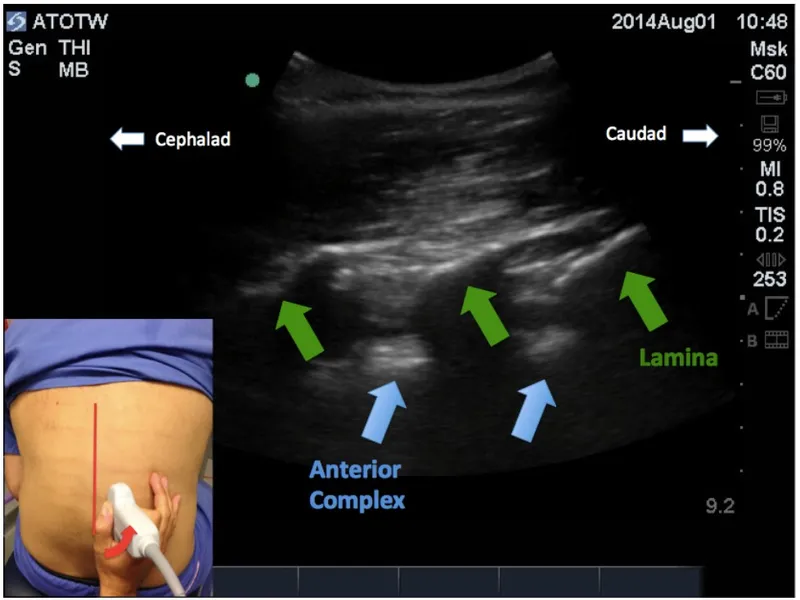

- Paramedian Sagittal: Interlaminar view ("sawtooth" laminae).

- Sagittal Paramedian View: "Sawtooth" appearance of laminae; identifies interlaminar spaces.

- Paramedian Sagittal (PMS): "Sawtooth" sign (laminae), ligamentum flavum-dura complex.